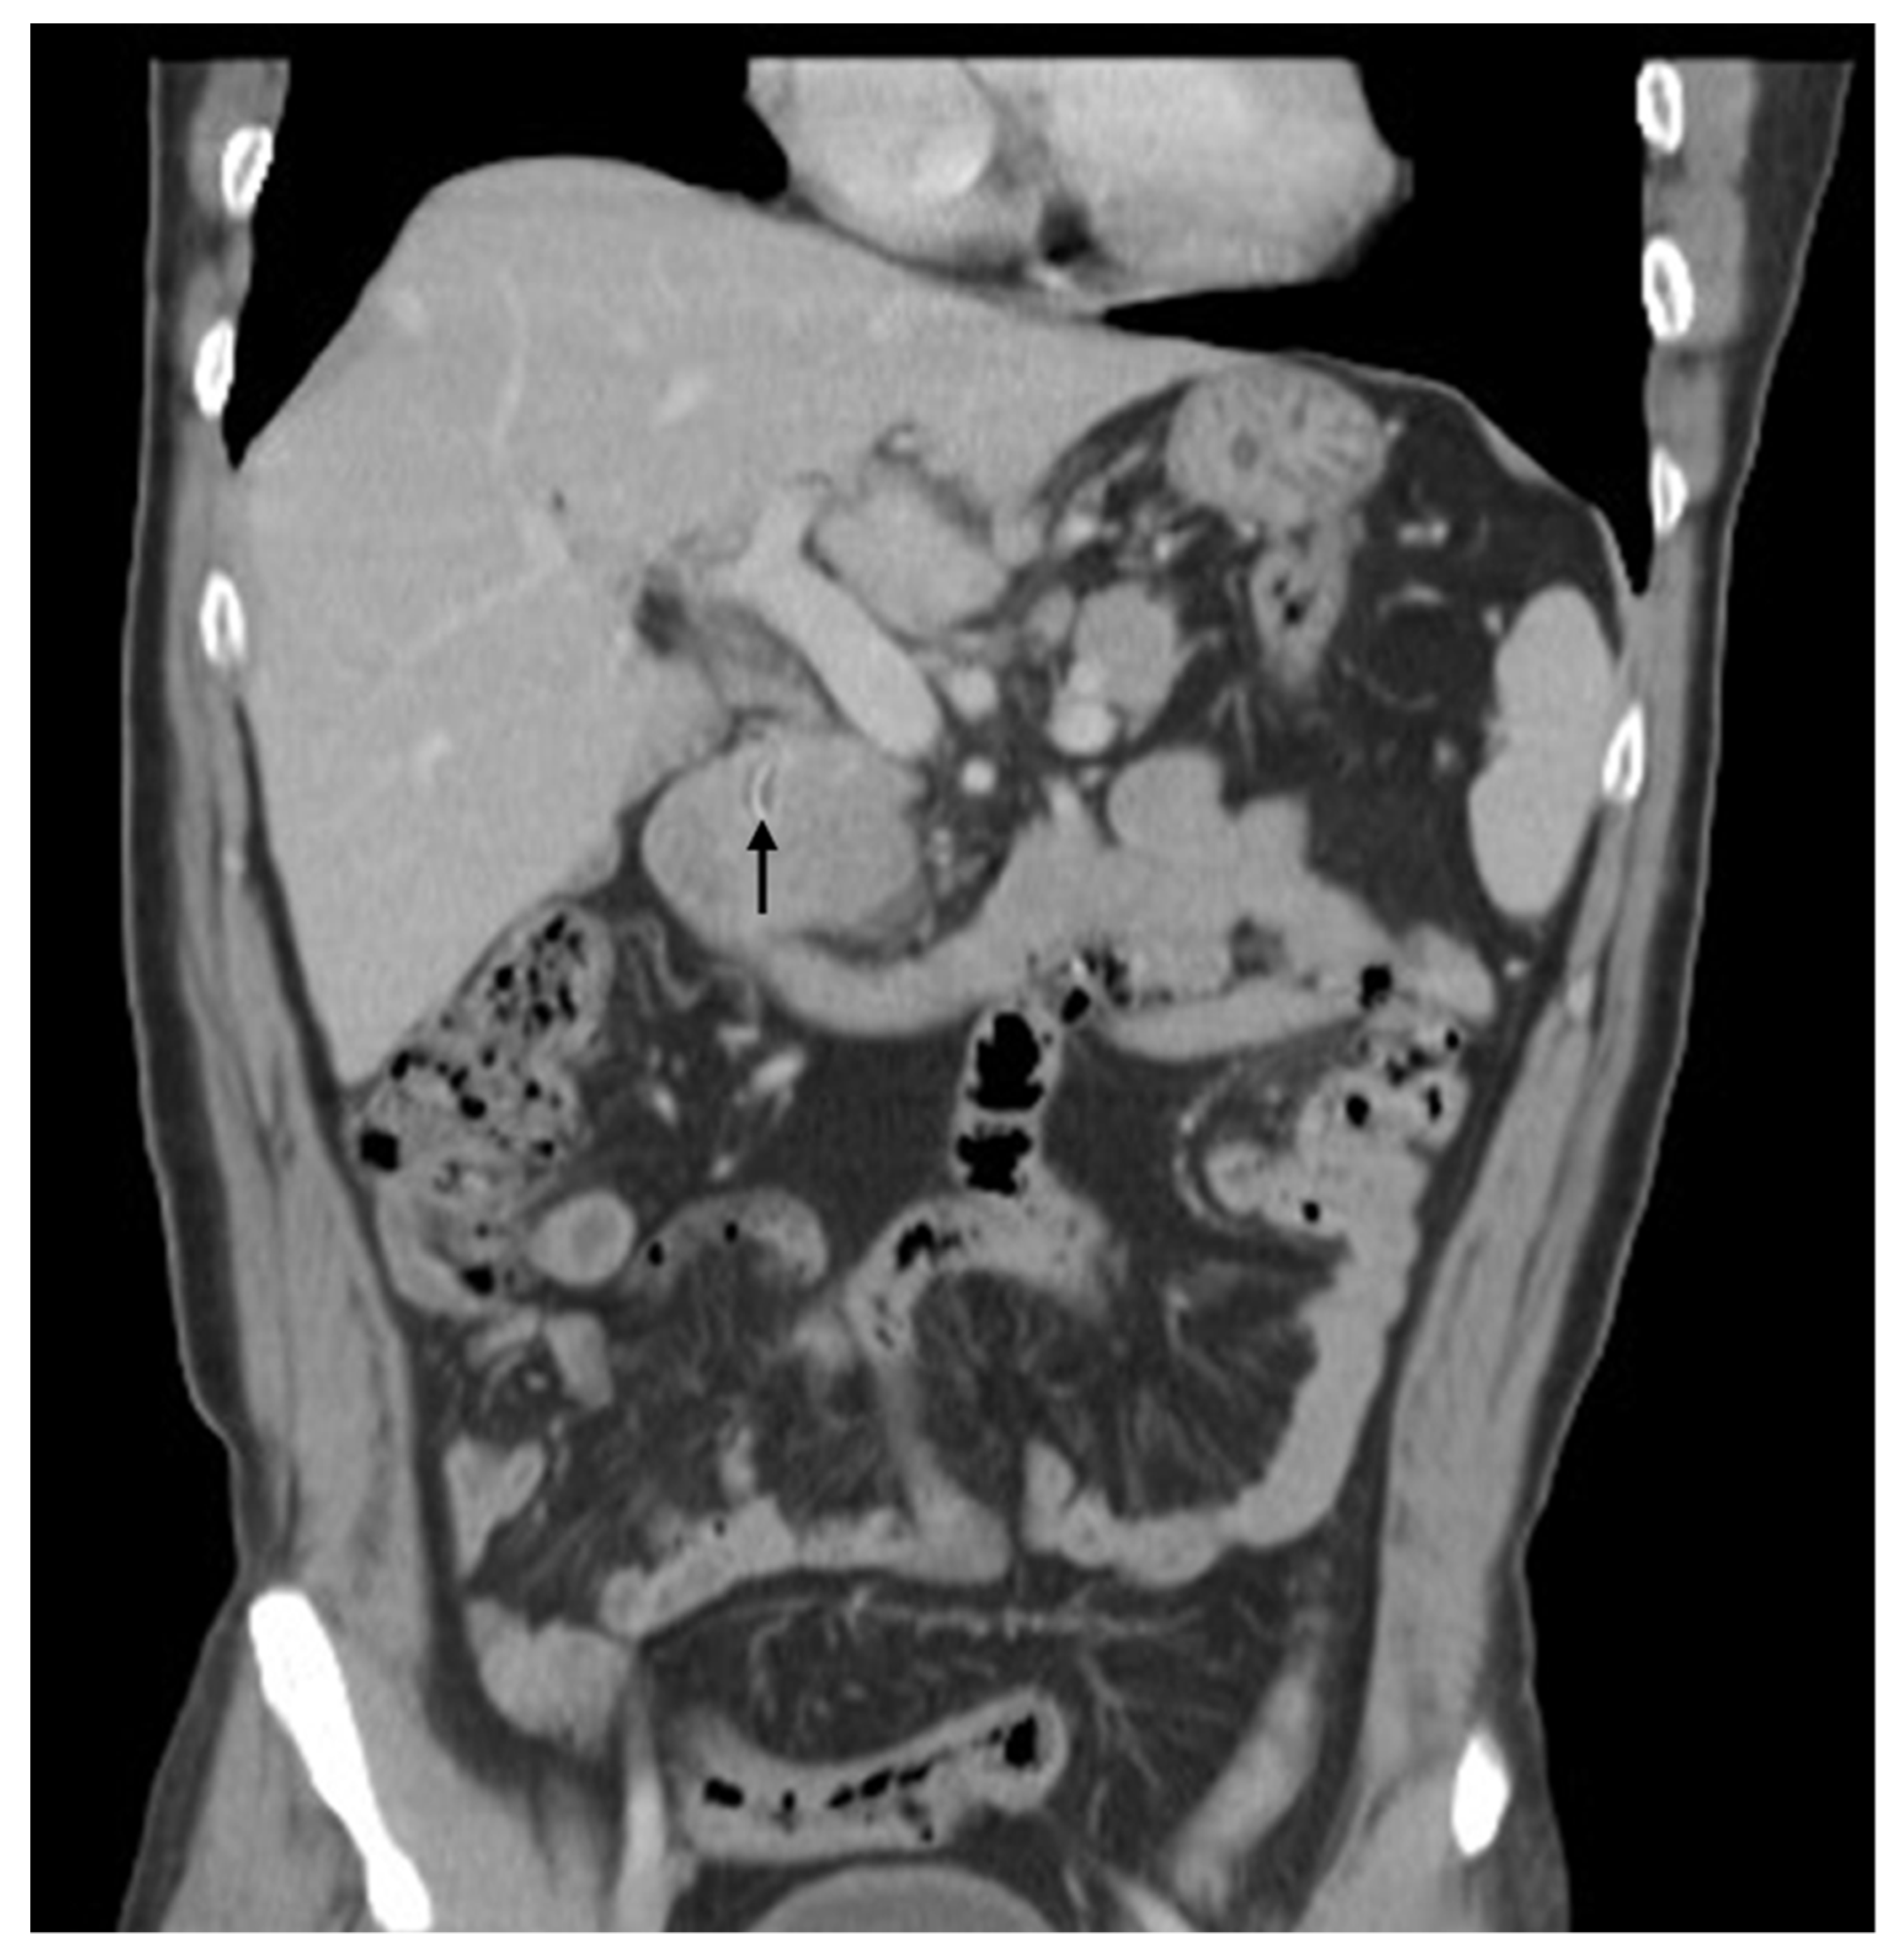

Figure 1. A computed tomography (CT) scan of the abdomen demonstrated abscess over the left lobe of the liver and a linear curve of high-density material within a mass. A 58-year-old man presented at our hospital with right upper-quadrant pain and fever. He had undergone laparotomic cholecystectomy and choledochojejunostomy 28 years prior at another hospital. He had been healthy until 3 days before his admission, when his symptoms appeared. A computed tomography (CT) scan of the abdomen demonstrated abscess over the left lobe of the liver and a linear curve of high-density material within a mass (Figure 1; arrow). The patient received antibiotics and underwent aspiration of liver abscess. Endoscopic retrograde cholangiopancreatography (ERCP) was performed after the symptoms and signs had subsided. ERCP depicted mild dilatation of the CBD and choledojejunostomic fistula of the middle CBD. The patient underwent a biopsy forceps, which removed a 1.7 cm curved, linear, rusty, metallic surgical suture needle containing bile (Figure 2). We examined the patient’s abdominal radiographs, which revealed that the needle was on the right side of the third lumbar spine vertebra (Figure 3; arrow). We followed up with abdominal radiography and detected no further evidence of the needle. The patient was discharged without further events.